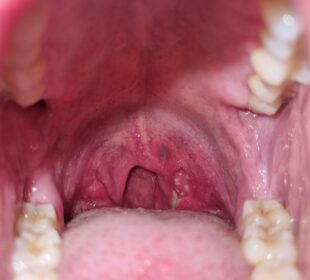

Streptokokinis faringitas – tai bakterinė infekcija, dažniausiai pasireiškianti gerklės skausmu, karščiavimu bei tonzilių ar užpakalinės gerklės dalies patinimu. Nors šią ligą lengva ...2026 6 sausioLytiniu keliu plintančių infekcijų požymiai ir simptomai